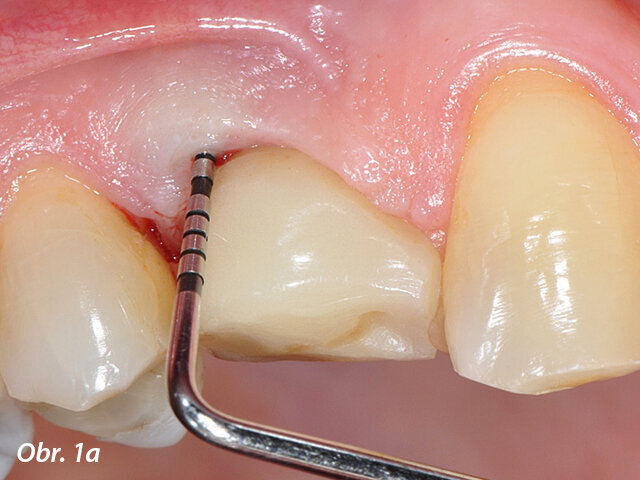

Periimplantitidou postižený implantát v pozici zubu 14 s patrnou patologickou hloubkou sondáže: a) implantát opatřený korunkou

Periimplantitidou postižený implantát v pozici zubu 14 s patrnou patologickou hloubkou sondáže: b) stav po sejmutí korunky